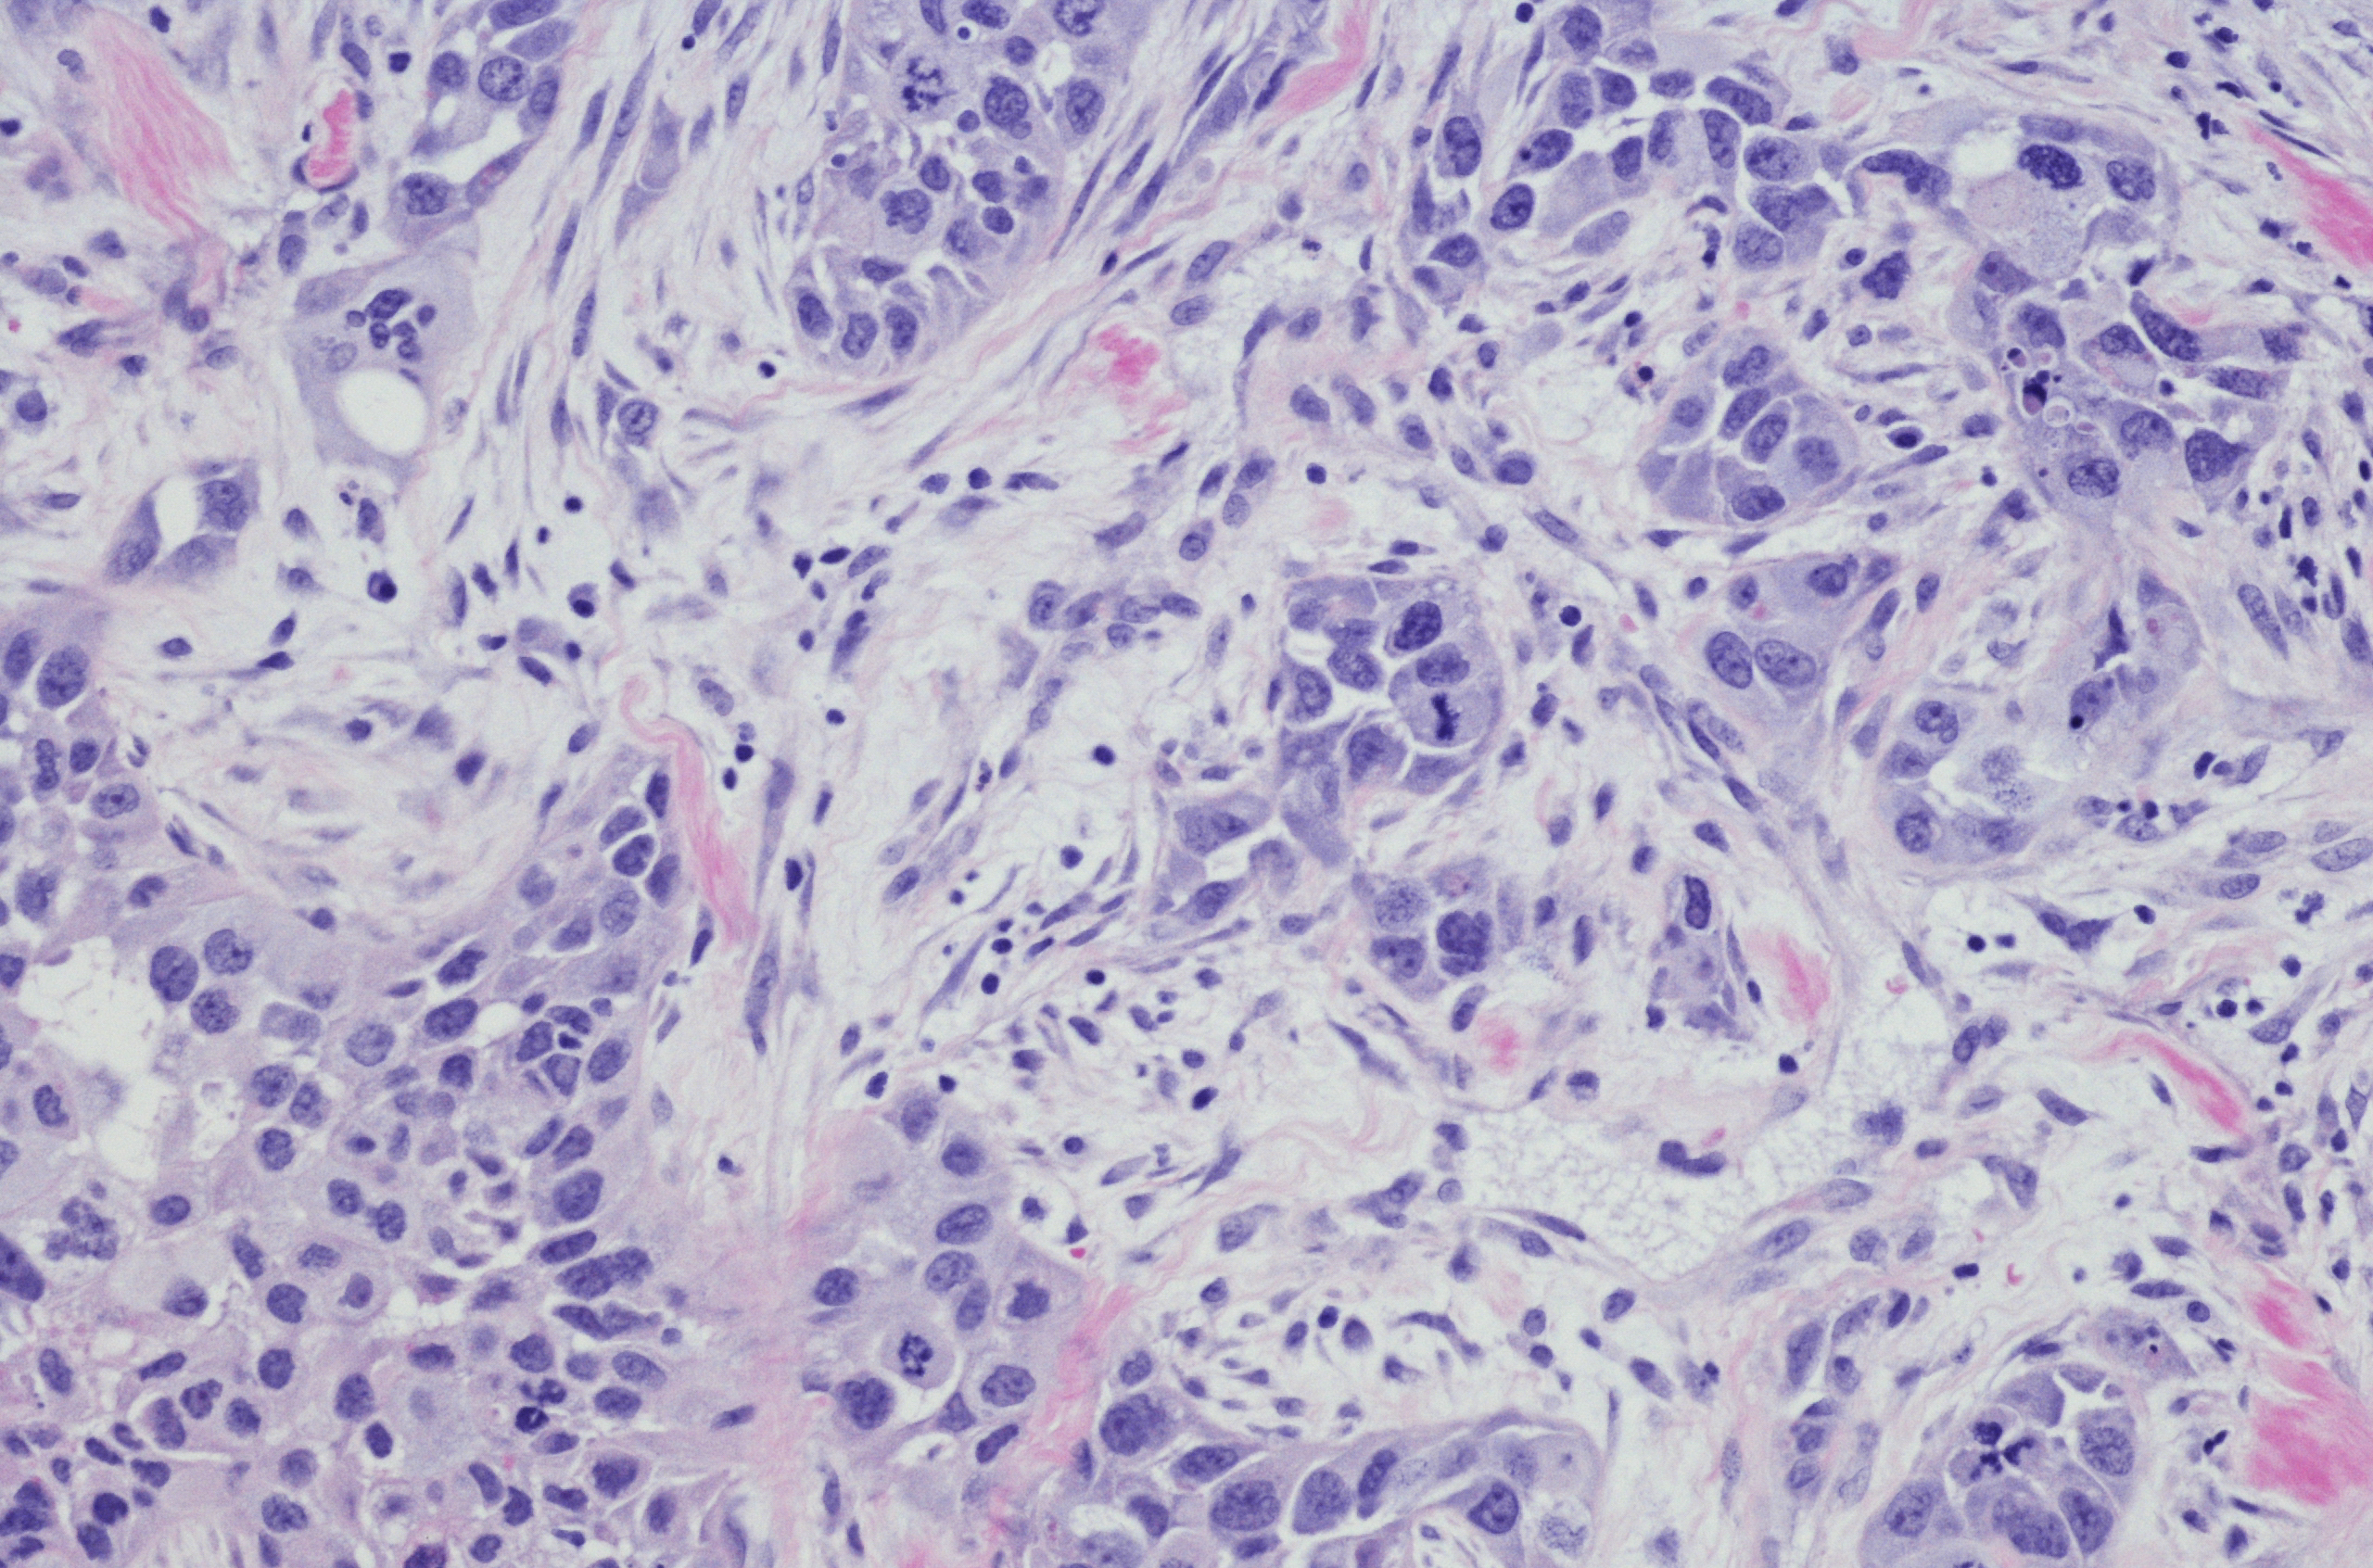

The term ‘triple negative’ is used to describe a type of breast cancer that does not have any of the three receptors commonly found on breast cancer cells. These receptors are:

Because of its triple negative status (Oestrogen Receptor negative, Progesterone Receptor negative and Human Epidermal Growth Factor Receptor 2 negative) this cancer type generally does not respond to receptor targeted treatments.

The BRCA1 mutation is associated with a higher risk for triple negative breast cancer. However, not all breast cancers caused by BRCA mutations are triple negative. BRCA2 mutations are more likely to be present in oestrogen receptor positive (ER+) breast cancer.